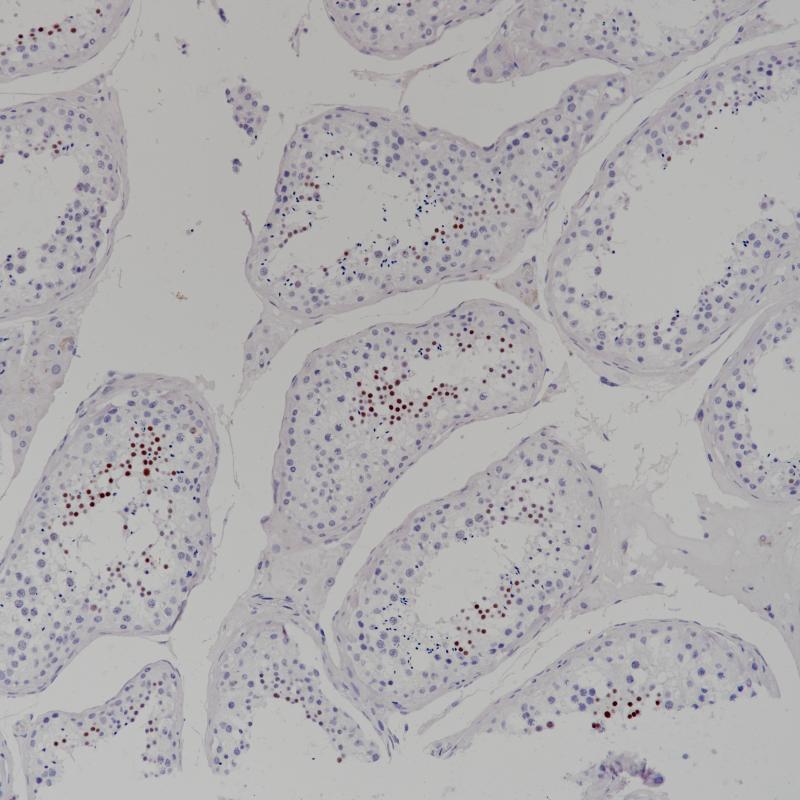

睾丸NUT1(BP6221)染色

睾丸NUT1(BP6221)染色 (2)

NUT1

重组兔单克隆抗体

睾丸核蛋白(NUT1或NUTM1)是15号染色体上的NUTM1基因编码的核蛋白,通常在睾丸组织中表达。NUT癌(原NUT中线癌)发生在NUTM1与溴区结构域(BRD)家族基因融合后,约75%的病例发生。NUT癌可以是肿瘤、肉瘤、淋巴瘤和其他类型的肿瘤,通常在头部、颈部或纵隔形成。NUT1抗体主要用于中线癌的诊断。

阳性对照

睾丸

亚细胞定位

细胞核

FFPE

HIER

1:100-1:200